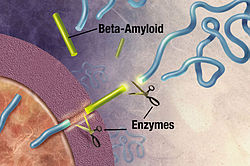

Alzheimer’s Dementia is the most common form of dementia, accounting for 60-80% of all dementia cases worldwide. While many people think of it simply as “memory loss,” Alzheimer’s Dementia is actually a complex brain disorder that affects thinking, behavior, and the ability to perform everyday activities. The disease develops when abnormal protein deposits, amyloid plaques, and tangles build up in the brain, disrupting communication between brain cells and eventually causing them to die. This process typically begins years before symptoms become noticeable, which is why early detection and understanding of Alzheimer’s Dementia is so crucial for families.

While there’s currently no cure for Alzheimer’s Dementia, several treatment options can help manage symptoms and potentially slow progression. Medications like cholinesterase inhibitors and memantine can help with cognitive symptoms in some people.

Non-drug approaches are equally important in Alzheimer’s Dementia care. Regular physical exercise, social engagement, cognitive stimulation, and maintaining good overall health can all contribute to a better quality of life. Music therapy, art therapy, and pet therapy have shown particular promise in helping people with Alzheimer’s Dementia maintain emotional connections and express themselves. Research into Alzheimer’s Dementia continues advancing, with scientists exploring everything from new medications to lifestyle interventions that might prevent or delay the onset of symptoms. While we wait for breakthrough treatments, focusing on quality of life and meaningful connection remains the most important gift we can give our loved ones.